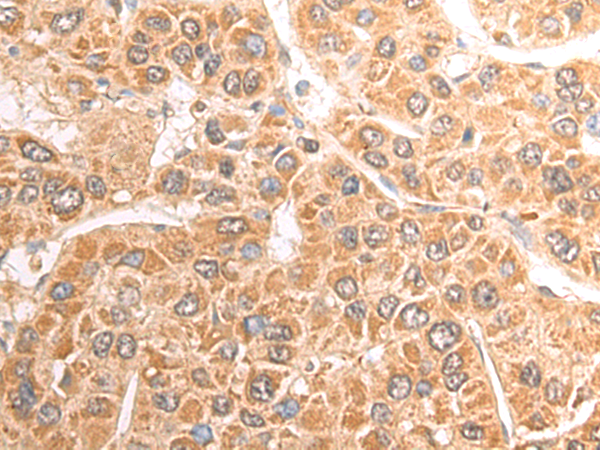

分类: 科研抗体货号: P06951别名: MEH; EPHX; EPOX; HYL1应用: IHC反应种属: Human, Mouse, Rat